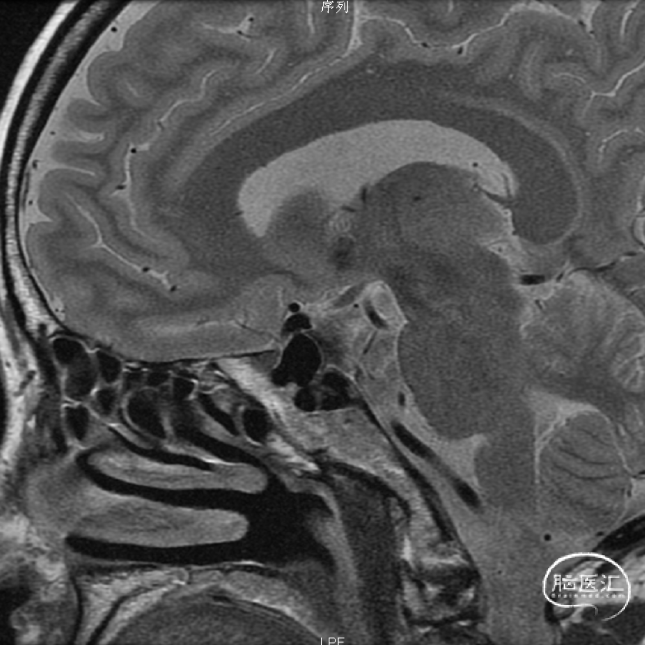

术前影像学检查结果

术前MRI

术前MRA